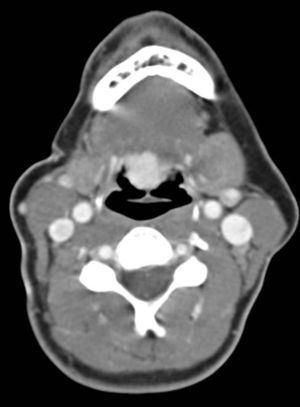

Image IQ: 50-year-old with History of Breast Cancer for Neck CT

ByMatthew Minn, MD,Erini Makariou, MD

January 22nd 2014

• Image IQ: 50-year-old with History of Breast Cancer for Neck CT

Published: January 22nd 2014 | Updated: